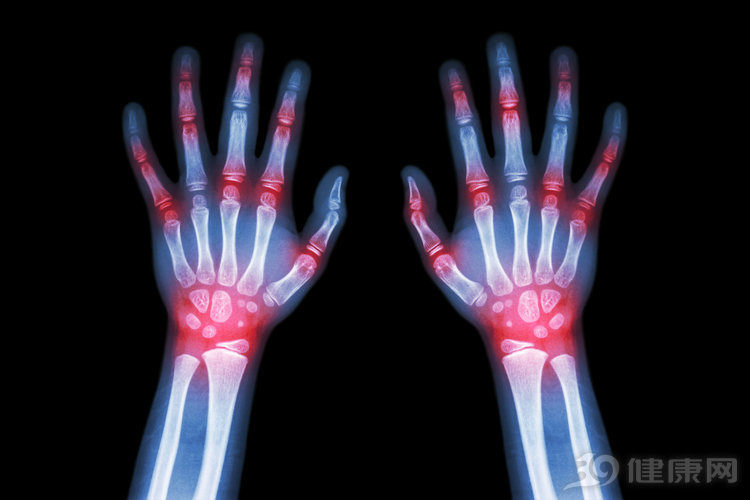

有效阻止关节破坏,关键在于早期诊断和规范治疗。该病主要侵犯小关节,当出现多关节的肿痛,尤其是手指、手腕出现肿痛,一定要警惕类风湿关节炎。

规范治疗则抓住类风湿关节炎起病的三个月内,这是国际公认的最佳治疗时机。不仅强调使用控制症状的药物,更要重视使用缓解病的抗风湿药。